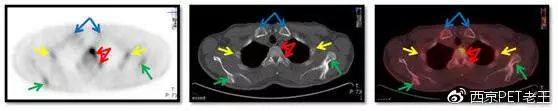

我们又把CT调整到骨窗,看骨骼病变的情况,可以看到全身绝大部分骨骼都有转移,但骨质结构破坏不明显(中列),说明这种是早期的骨转移,如下图:

红色箭头:胸椎及附件转移;黄色:肋骨转移;绿色:肩胛骨转移;蓝色:锁骨胸骨端转移